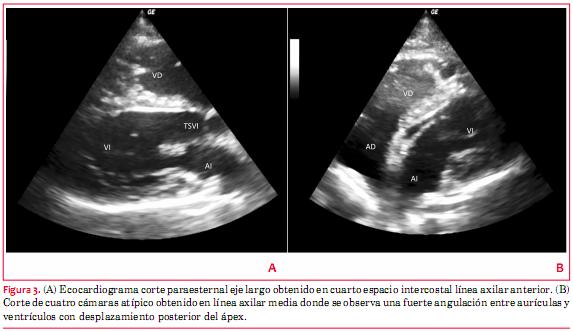

El ecocardiograma Doppler (figura 3) mostró un desplazamiento a izquierda de las ventanas acústicas. La imagen paraesternal se obtuvo en la línea axilar anterior, no se pudo obtener una verdadera ventana apical, pero una imagen atípica de cuatro cámaras se obtuvo desde línea axilar media. La alineación entre aurículas y ventrículos estaba alterada con una fuerte angulación debida al desplazamiento de ambos ventrículos hacia la izquierda y hacia atrás. Las cavidades izquierdas tenían dimensiones normales. El movimiento del septum interventricular era paradójico y la función sistólica global del ventrículo izquierdo se estimó normal. La válvula mitral estaba engrosada, con ligero prolapso de hojuela anterior e insuficiencia mitral leve. El ventrículo derecho estaba ligeramente dilatado con función sistólica normal.

El ecocardiograma no es capaz de identificar confiablemente la presencia o ausencia de pericardio. Sin embargo, aporta datos indirectos pues las ventanas acústicas están desplazadas hacia la izquierda, obteniendo la imagen paraesternal en una topografía cercana a la axila y, aún más a la izquierda, una imagen de cuatro cámaras atípica con orientación posterior de la punta del corazón. El septum ventricular suele tener movimiento paradójico y la función sistólica del ventrículo izquierdo es normal. El ventrículo derecho suele verse dilatado, hallazgo que puede ser simulado por la anomalía posicional(4,8).